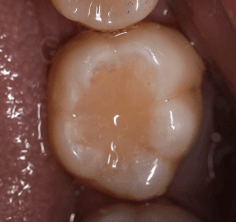

Case Study 3

This case involved a direct composite restoration to manage occlusal caries secondary to an existing GIC. Rubber dam isolation provided excellent moisture control and visibility, allowing for precise cavity preparation and layering technique. Upon reviewing the completed restoration in natural light as well as the photographs, a more accurate shade match would’ve been advantageous. The case reinforced the importance of good isolation for predictable bonding and also helped build my confidence in restoring posterior teeth with attention to anatomy and occlusion.

Case Study 2

This case involved a direct composite restoration to manage occlusal caries secondary to an existing GIC. Rubber dam isolation provided excellent moisture control and visibility, allowing for precise cavity preparation and layering technique. Upon reviewing the completed restoration in natural light as well as the photographs, a more accurate shade match would’ve been advantageous. The case reinforced the importance of good isolation for predictable bonding and also helped build my confidence in restoring posterior teeth with attention to anatomy and occlusion.